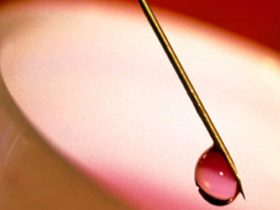

WEDNESDAY, Jan. 11, 2023 (HealthDay News) — Combined use of shape-sensing robotic-assisted bronchoscopy (ssRAB) with radial endobronchial ultrasound (r-EBUS) and cone beam computed tomography (CBCT) for lung lesions has high diagnostic accuracy for malignancy, according to a study published online Nov. 11 in Lung.

Kim Styrvoky, M.D., from the University of Texas Southwestern Medical Center in Dallas, and colleagues conducted a retrospective analysis of the first 200 biopsy procedures of 209 lung lesions using ssRAB combined with r-EBUS and CBCT.

The researchers found that the median lesion dimension was 19 mm, and the mean largest lesion diameter was 22.6 ± 13.3 mm. The prevalence of malignancy was 64.1 percent. ssRAB combined with advanced imaging had a diagnostic accuracy of 91.4 percent; sensitivity and specificity were 87.3 and 98.7 percent, respectively. The negative predictive value was 81.3 percent and the positive predictive value was 99.2 percent. Nondiagnostic sampling was performed at a rate of 11 percent. The only complication was pneumothorax, which occurred in 1 percent of procedures; 0.5 percent needed a chest tube.

“This retrospective study adds to the currently available body of literature suggesting that ssRAB in conjunction with advanced imaging modalities, such as r-EBUS and CBCT, is the next evolutionary step in guided bronchoscopy and provides an accurate and safe procedure for the evaluation of malignant and nonmalignant pulmonary lesions,” the authors write.